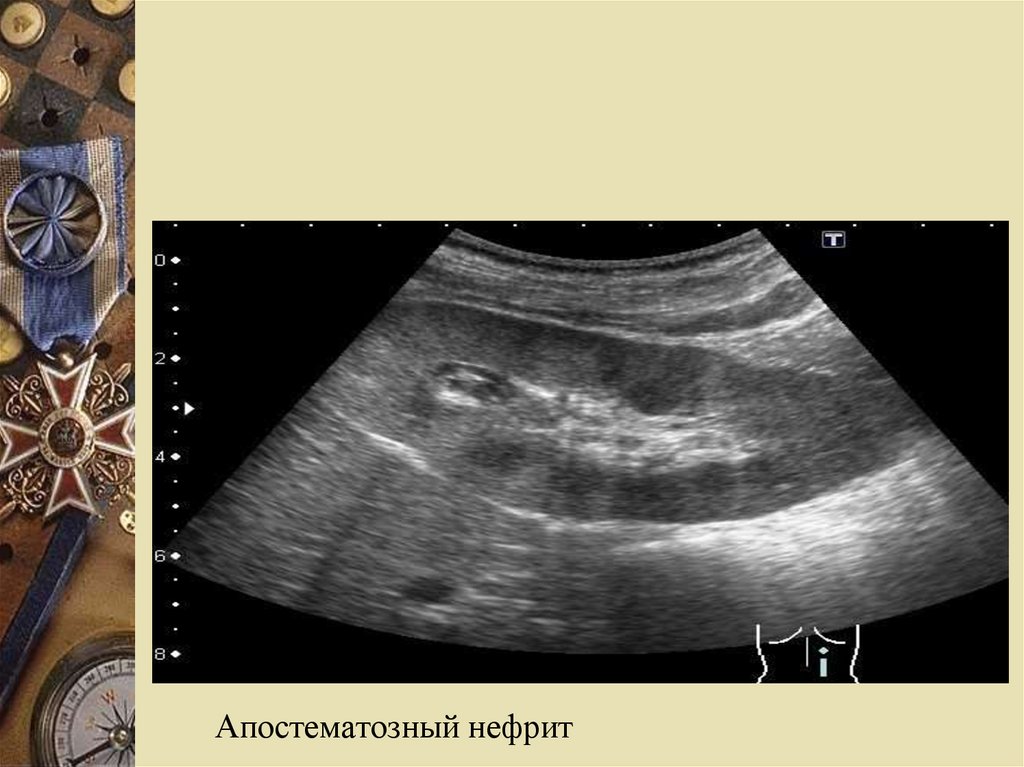

Апостематозный пиелонефрит: увеличение

почек в размерах, ограничение их подвижности

Апостематозный нефрит